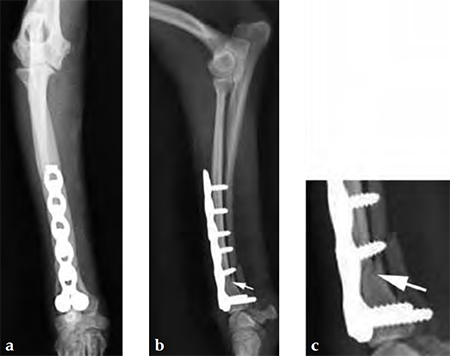

The dog was discharged from the hospital 2 days postoperatively with instructions for strict exercise restriction; the dog was ambulatory on all four limbs at this time, although lame on the right forelimb. The bandage was to be removed in about 57 days. The dog did very well and was reevaluated 8 weeks postoperatively, at which time radiographs revealed a healed radius and atrophic ulna (Fig 4 - the ulnar atrophy is the norm in the canine for this repair in these small dog breeds). The dog was fully ambulatory and without lameness at this time; however, there was a slight decrease in full flexion at the antebrachiocarpal jointagain, this is the norm with this repair due to the surgical dissection and plate placement under the extensor tendons, which does not cause any functional deficit in the dog. The dog was gradually returned to full activity over the ensuing 2 weeks. It is recommended that these dogs not be allowed to jump from heights (eg, bed, chair) as they are at increased risk for this fracture, regarding the opposite limb in this patient.